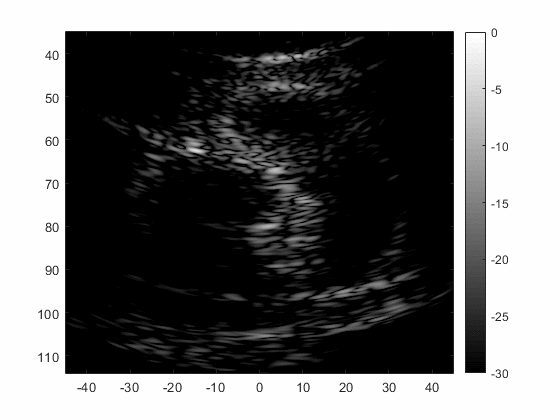

Kidney Imaging